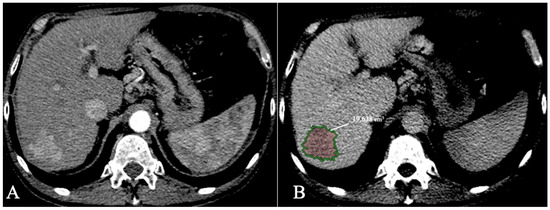

4.2. Segmentation

| Bousabarah et al. [70] | 2021 | Liver and HCC segmentation | MRI | DL (U-Net CNN) | 91% for liver 68% for HCC |